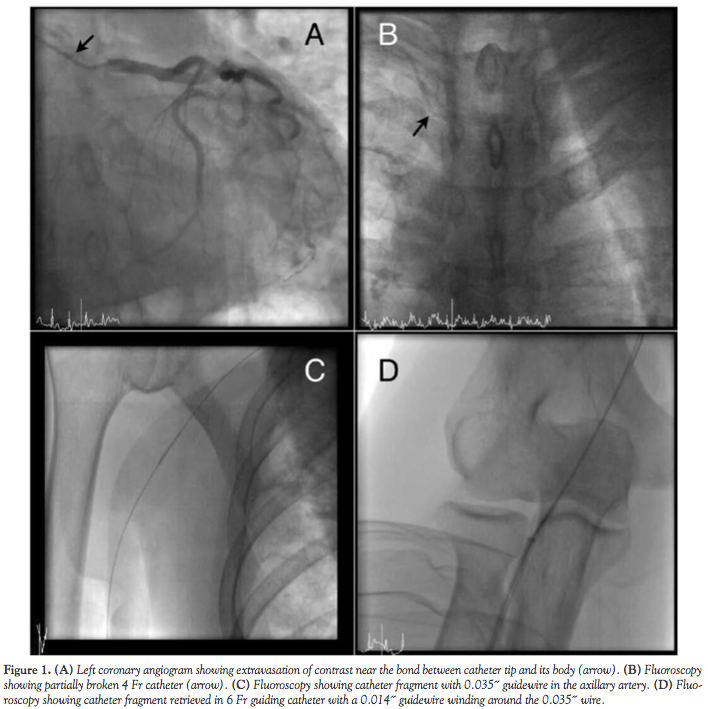

A 65-year-old male patient underwent coronary angiography via his right radial artery at our day care center because of positive result on treadmill test. During the left coronary angiogram, extravasation of contrast was noted near the bond between catheter tip and its body (Figure 1A, arrow). Fluoroscopy showed that the 4 French (Fr) catheter was partially broken (Figure 1B, arrow). A 0.035-inch J-tip wire was passed through the partially broken catheter and retrieval was attempted via a 4 Fr arterial sheath, but the catheter was completely broken (Figure 1C). After removal of the 4 Fr arterial sheath, a 6 Fr arterial sheath and a 6 Fr guiding catheter (Ikari Right, Terumo Corporation) was introduced over the 0.035-inch guidewire. A 0.014-inch standard percutaneous transluminal coronary angioplasty (PTCA) guidewire was introduced through the catheter fragment. The 0.014-inch guidewire twirled, winding around the 0.035-inch wire, and the catheter fragment was retrieved into a 6 Fr guiding catheter; the whole system was then successfully retrieved through the 6 Fr radial sheath (Figure 1D and Figure 2). A right coronary angiogram was performed using the other 4 Fr diagnostic catheter. The patient was discharged home on the same day uneventfully.